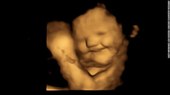

Pesquisa feita na Inglaterra ofereceu cápsulas com cenoura e couve orgânica à mulheres com até 36 semanas de gravidez; imagens de ultrassom mostram reação dos bebês

Os fetos podem fazer uma espécie de “cara de riso” no útero quando expostos ao sabor das cenouras consumidas por sua mãe e dão uma resposta com “cara de choro” quando expostos à couve, de acordo com um estudo publicado na revista Psychological Science, divulgado nesta quarta-feira (21).

Após um período de espera de 20 minutos após o consumo, as mulheres foram submetidas a ultrassonografias 4D, que foram comparadas com imagens 2D dos fetos.

O puxão do canto dos lábios, sugestivo de sorriso ou risada, foi significativamente maior no grupo da cenoura em comparação com o grupo de couve e controle.

Enquanto movimentos como levantar o lábio superior, baixar o lábio inferior, pressionar os lábios e uma combinação desses – sugestivos de cara de choro – foram muito mais comuns no grupo da couve do que nos outros grupos.